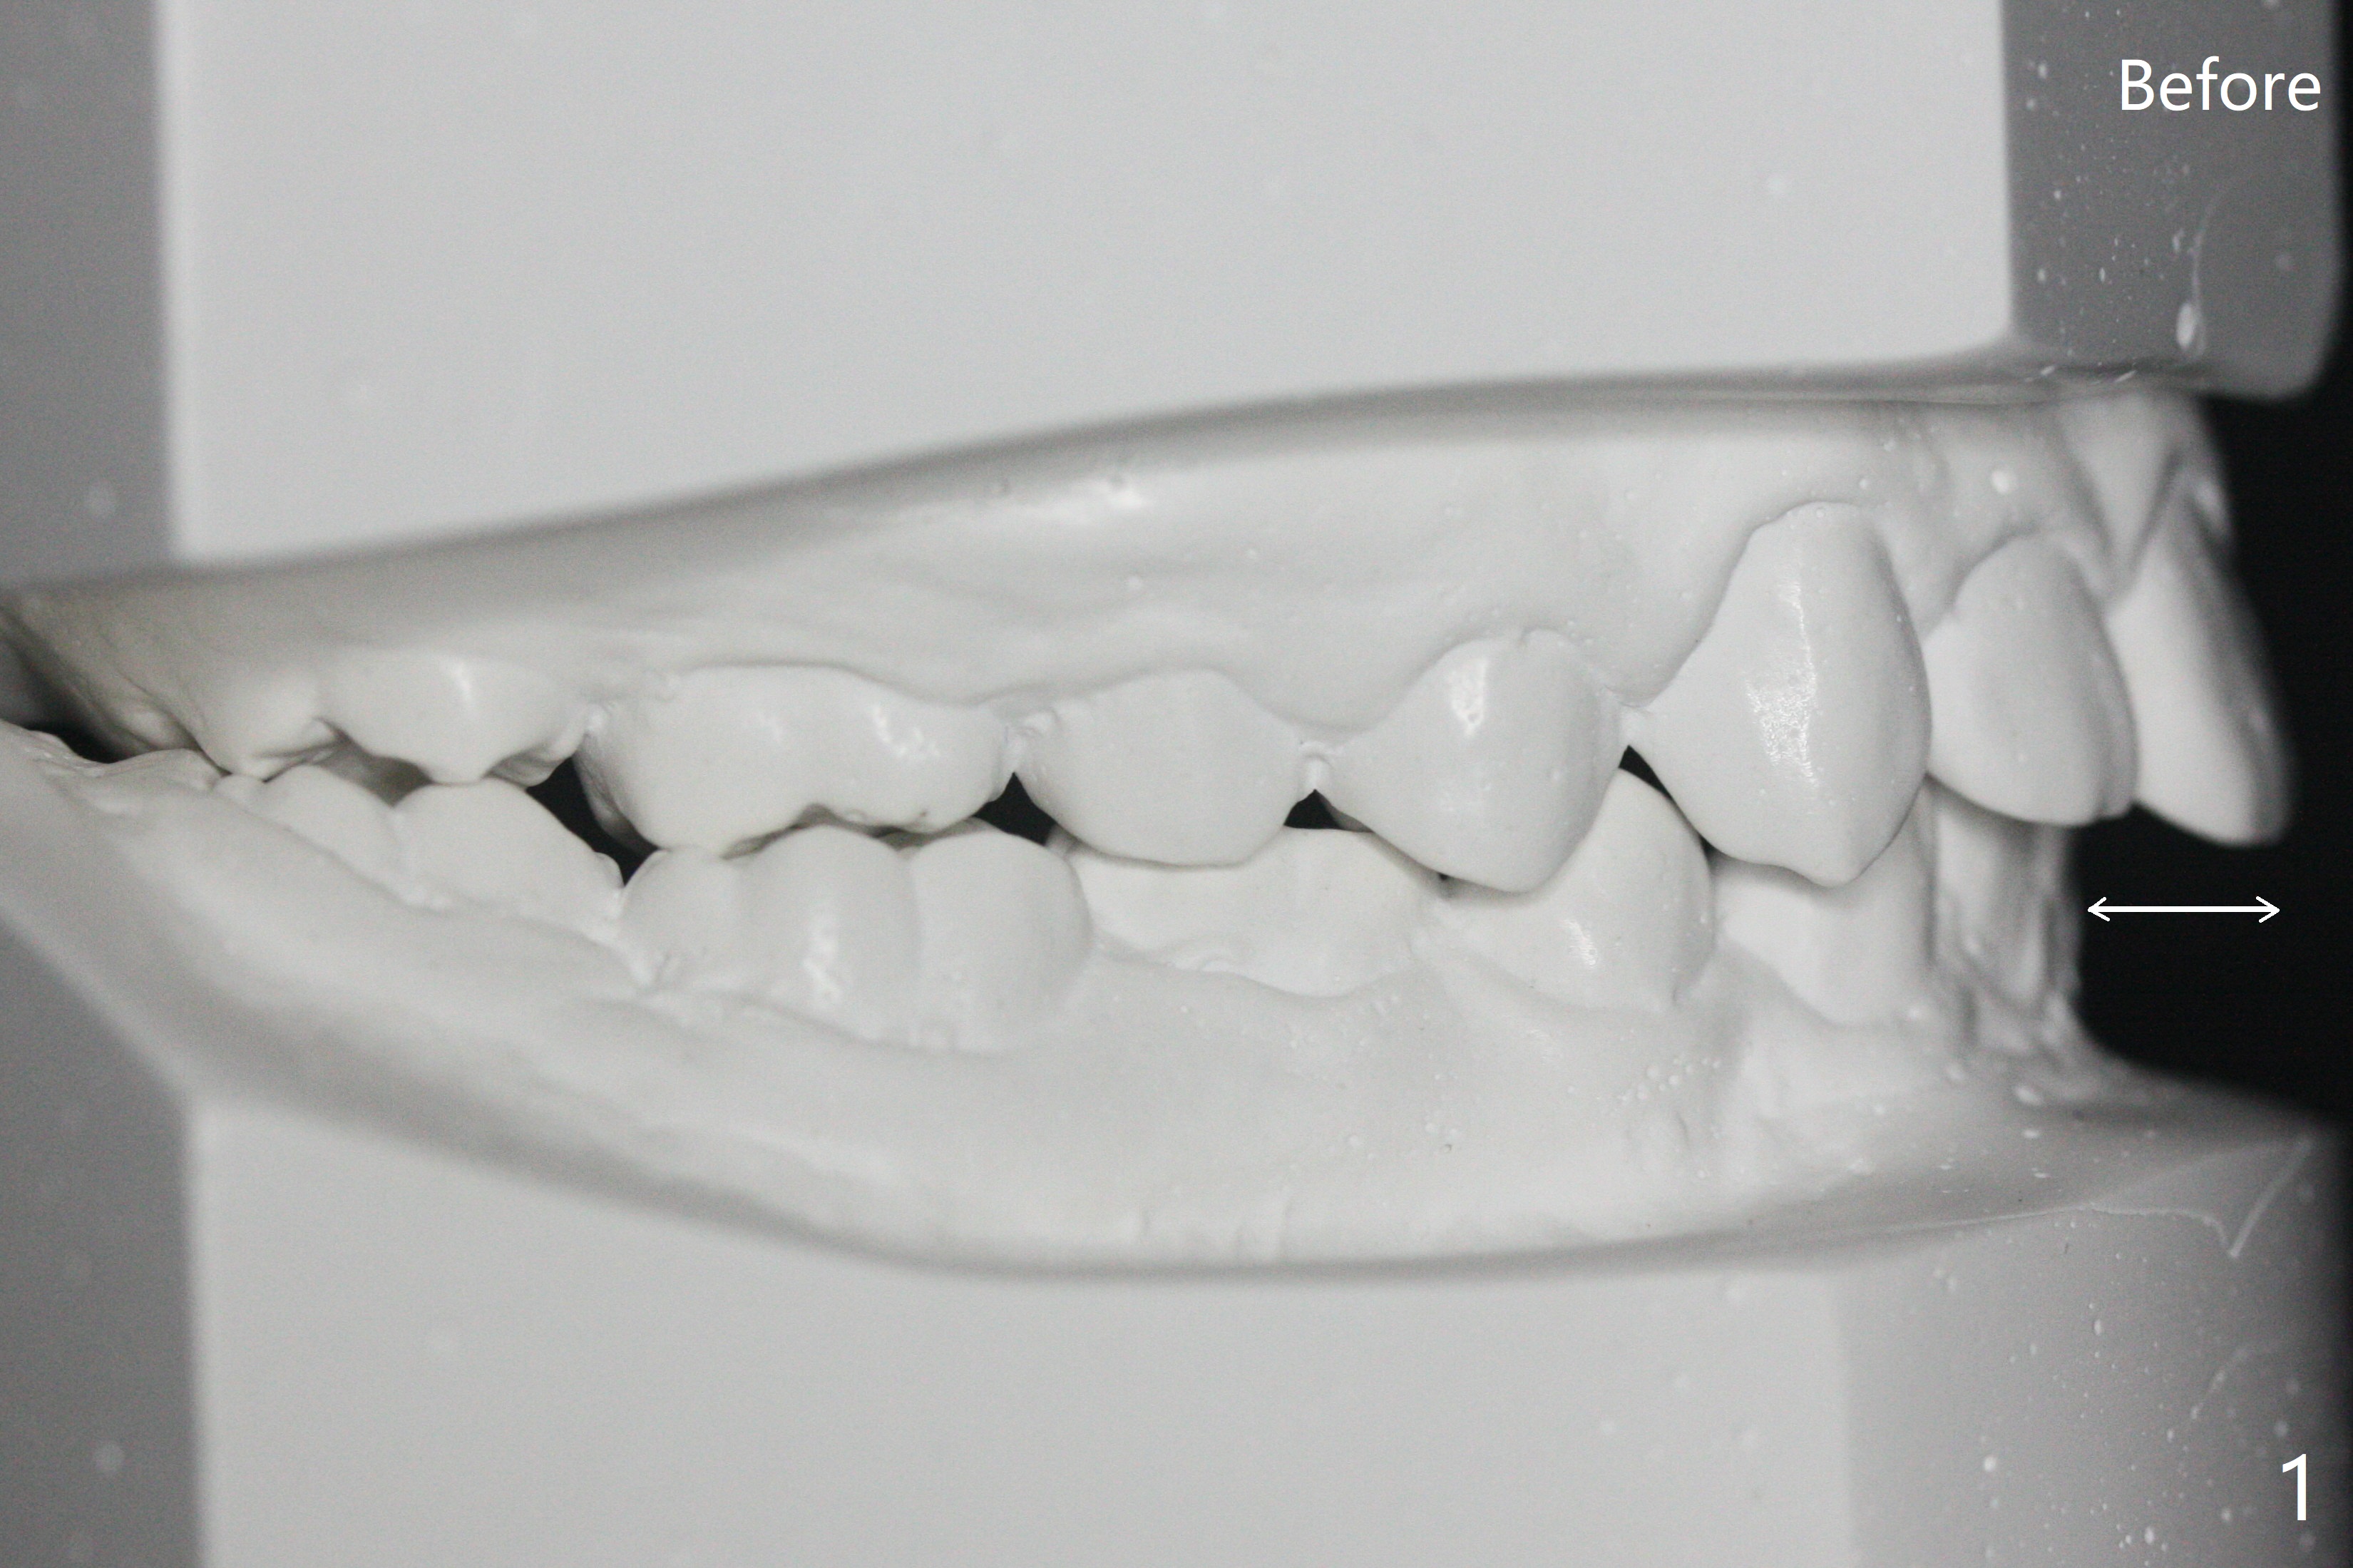

One-year-8-month orthodontic treatment reduces anterior overjet (Fig.1 (double arrows),1', with facial profile improvement), corrects right 1st molar cross bite (Fig.2,2') and dental midlines (Fig.3,3'), closes the diastema between UL3 and 4, extrudes UL5 (Fig.4,5,4',5'), and increases space for future implant at LL4 (Fig.6,6'). In fact large arches with distemata make the treatment possible! Extrusion of UL5 leads to root development (Fig.7, 7' (R)). The increased space at LL4 (Fig.7' *) appears insufficient for an implant.